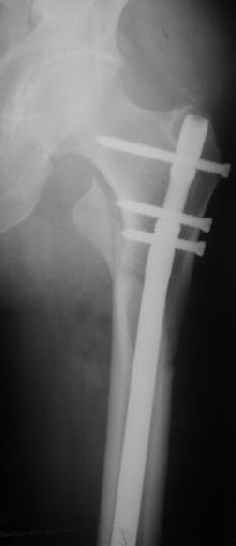

Могу скромно напомнить о существовании стержня нашей модификации.

В частности, на проксимальном конце сделано еще одно дополнительное статическое отверстие. Можно ввести в проксимальном отделе 4 винта, из них 3 статические (2 в круглые отверстия и 1 по нижнему краю овального). Картинки в приложении. На дистальном конце стержня тоже кое-что улучшено. Спрашивайте в аптеках, как говорится. Выпускается предприятием "ЦИТО" (Москва), то есть это малобюджетное решение.

Это было года 2,5 назад, мы тогда еще уточняли возможности шинирования с угловой стабильностью гвоздем с поперечным расположением винтов при переломах проксимального отдела бедра. Пациенту не пришлось приобретать намного более дорогой рекон или проксимальный гвоздь. В приложении еще несколько примеров применения того гвоздя при высоких переломах бедра, в том числе с более латеральной точкой входа. Гвоздь изгибаем для этого.